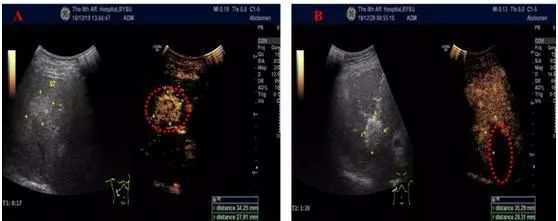

患者张某,65岁,直肠癌肝转移患者,超声提示肝内多发转移灶,最大病灶41x24mm,传统手术切除困难。患者在获悉微波消融术这一治疗方法后,欣然接受超声引导下肿瘤微波消融治疗。术中,超声造影证实肝内转移灶消融完全。患者术后情况良好,术后第二天就可以下床活动。

A图消融前超声造影,红圈为肝内其中一个病灶

B图消融后超声造影,红圈为肿瘤消融区